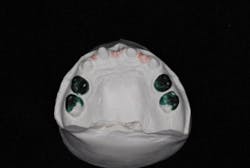

Before a treatment plan can be developed, it is crucial to make an accurate dental diagnosis. Although the patient was only nine years old, it was necessary to outline diagnostic protocols to thoroughly evaluate and diagnose. We started with a complete exam, diagnostic photographs, and study casts mounted in centric relation (figures 9a and 9b). Through these records, we were able to determine the patient’s ideal tooth position to satisfy her esthetic goals. We discussed treatment options on how to achieve these results with both the patient and the parents (figure 10).